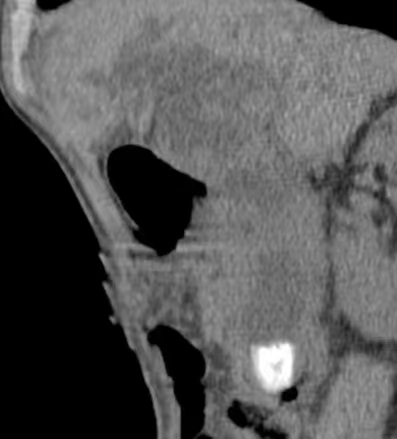

术前CT显示胆总管1.7X2.2cm结石影。